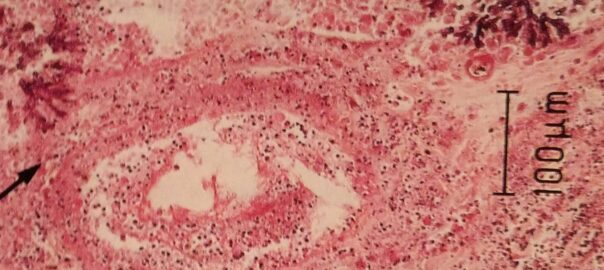

Eine Aspergillose ist eine Schimmelpilz-Erkrankung verursacht durch den Pilz Aspergillus (auch Giesskannenschimmel genannt). Es befällt zumeist unbemerkt die Lunge. Auch die Haut wird öfters befallen, ist aber augenscheinlich schneller erkennbar. Ohren und Nasennebenhöhlen können auch befallen werden.

Die Gefahr der invasiven Aspergillose mit raschestem Verlauf als derzeit häufigste und gefürchtetste Pilzkrankheit mit höchster Mortalität bei hämatologischen Patienten und nach Organ-Transplantation (z.B. Herz) fordert eine ständige Überwachung, spätestens mit Beginn der Immunsuppression.